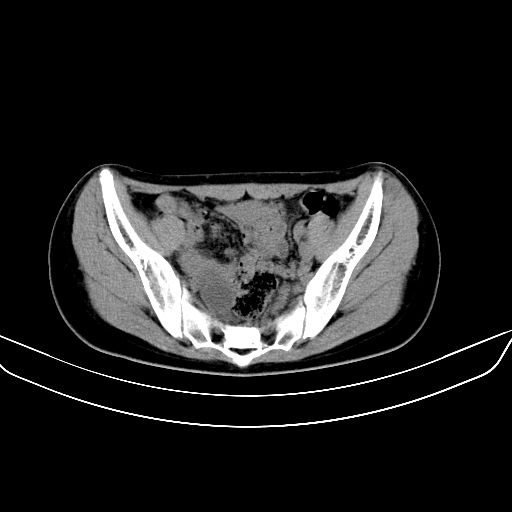

以下是引用zsl6918在2008-7-11 21:40:00的发言:[br]双侧骶髂关节骨质破坏以下三分之一为主,符合强直性脊柱炎表现

以下是引用zhangzhongshou在2008-7-11 21:41:00的发言:[br]患者是女性,hla-b27抗原(—),首先不太考虑强直性脊柱炎,建议查类风湿因子,骶髂关节改变考虑类风湿性关节炎可能性大,建议进一步检查。